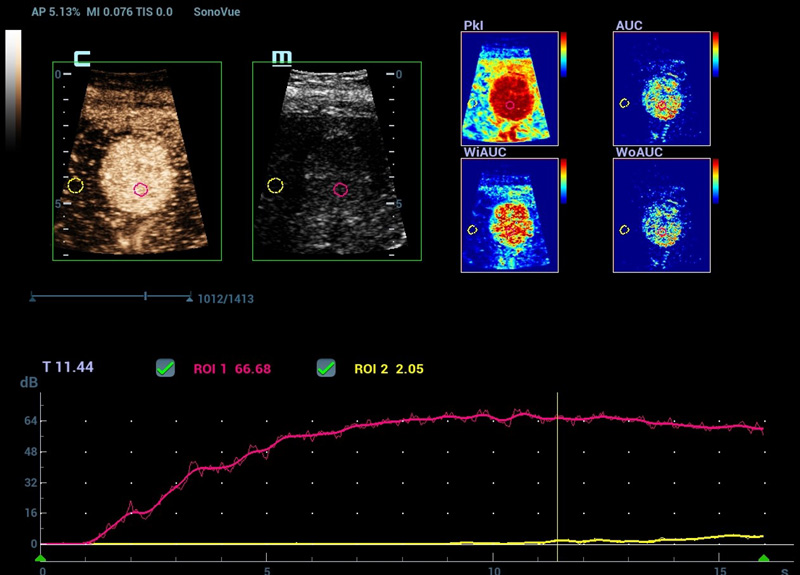

Nuova analisi quantitativa CEUS

Nuova QA CEUS tumore maligno al seno

La curva tempo-intensitĂ offre un'analisi quantitativa dell'imaging CEUS. La Nuova QA CEUS fornisce strumenti di analisi quantitativa all'avanguardia per la valutazione dei tumori e la ricerca clinica.